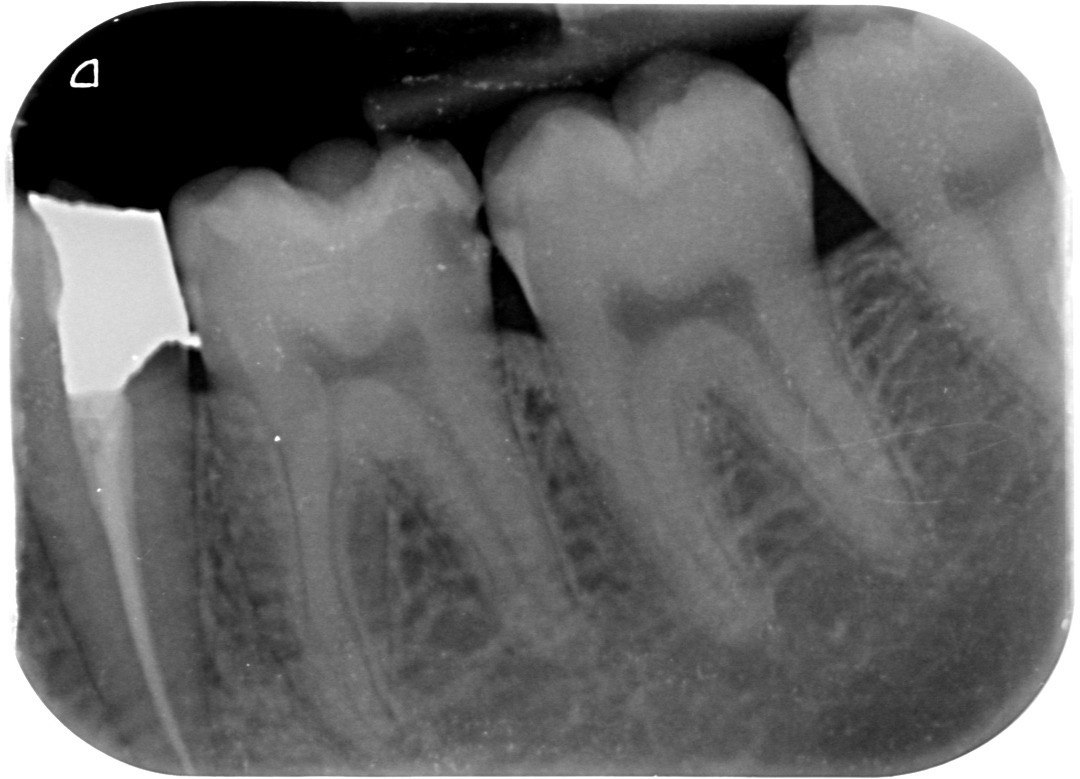

1. Which surfaces shows dental caries?

2 / 50

2. Which surface needs restoration?